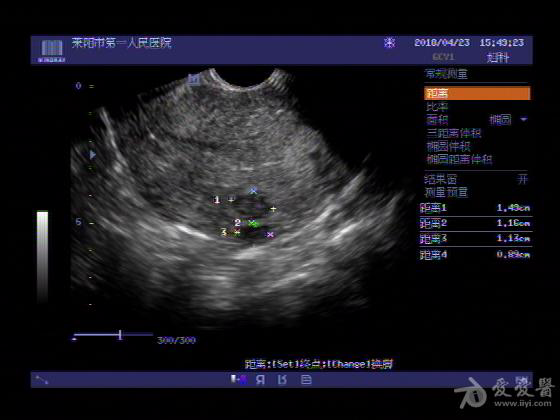

女,48岁,月经量多,两个月,一年前出现过类似现象,刮宫吃药后缓解。

超声可见:子宫内膜显著增厚,后肌壁内膜可见范围约3.27X0.90CM低回声区,CDFI显示较丰富线样血流,宫底宫腔内见类**状低回声结节。前肌壁见多发类圆形低回声结节。

超声提示:子宫内膜增厚(建议刮宫病理),子宫多发肌瘤

病理结果:内膜增生